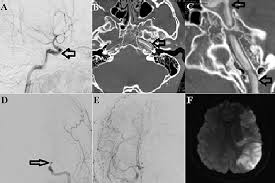

Scad most commonly affects women in their 40s and 50s. Dissection of the vertebral artery occurs in 1 per 100,000 of the population, however it makes up about 25% of all cerebral events in those less than 40 year of age (2). Approximately 2.5% of all strokes in the u.s. A carotid dissection is a tear in the artery wall that allows blood to flow between the wall layers. It is mainly characterised by local signs such as headache. A carotid dissection can be due to injury. These are a set of paired arteries at the sides of your neck. Carotid dissection is about 3 times commoner than vertebral. It can be due to injury. Spontaneous dissection of the carotid artery occurs in 3 per 100,000 of the population annually (1). Carotid artery dissection is a tear in one of the layers of the artery wall. Soldiers often engage in leisure, training, and combat activities that place them at risk for sustaining an injury that causes a carotid artery dissection. If a diagnosis of spontaneous internal carotid artery dissection is under consideration, laboratory studies are largely irrelevant for diagnostic purposes.

Carotid artery dissection is a tear in one of the layers of the artery wall. Spontaneous dissection of the carotid artery occurs in 3 per 100,000 of the population annually (1). The natural history of cerebrovascular fmd is unknown and management of symptomatic patients can be challenging. Blood vessel walls normally have three layers, and a tear in any of these can allow blood to flow into the resulting space, causing the vessel to bulge. Carotid artery dissection is a major cause of cerebral infarction in the young. Carotid artery dissection has been described after chiropractic manipulation. May occur spontaneously, or in the setting of major/minor neck trauma (mvc (classically a seat belt injury)) vs. Scad can slow or block blood flow to the heart, causing a heart attack, abnormalities in heart rhythm or sudden death.

Arterial dissection is a tear of the inside of the artery. The tear that initiates the dissection may occur spontaneously or after injury. Medical imaging tests can help rule out other conditions with similar symptoms. The first portion of each carotid artery is the called the common carotid artery. These arteries supply blood to your brain. May occur spontaneously, or in the setting of major/minor neck trauma (mvc (classically a seat belt injury)) vs. Similarly, dissections affect distal parts of the extracranial vertebral artery, whereas atherosclerosis tends to involve the proximal segments C0338585) spontaneous or traumatic separation of the layers of the carotid artery wall. Carotid dissection is a tear in the carotid artery wall. But it's still a dangerous situation. I will elaborate in a few sentences. Blood vessel walls normally have three layers, and a tear in any of these can allow blood to flow into the resulting space, causing the vessel to bulge. It manifests with headache, neck pain, temporary vision loss, and/or ischemic stroke.